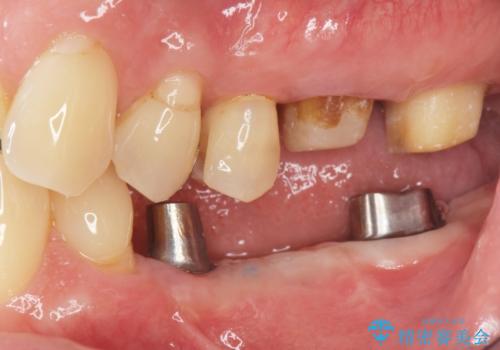

- 失ってしまった左下の奥歯にインプラント治療を受けたいと来院されました。

左下の欠損部には強度・表面性状に優れるストローマン社製インプラントを埋入し、合わせて噛み合う上顎の歯もクラウン再補綴による整備を行い安定した咬合関係の構築を目指します。

今回左下にインプラント治療を行うにあたり、対合する上顎の歯もいっしょに治療を行ったことで安定した咬合関係を構築することができました。